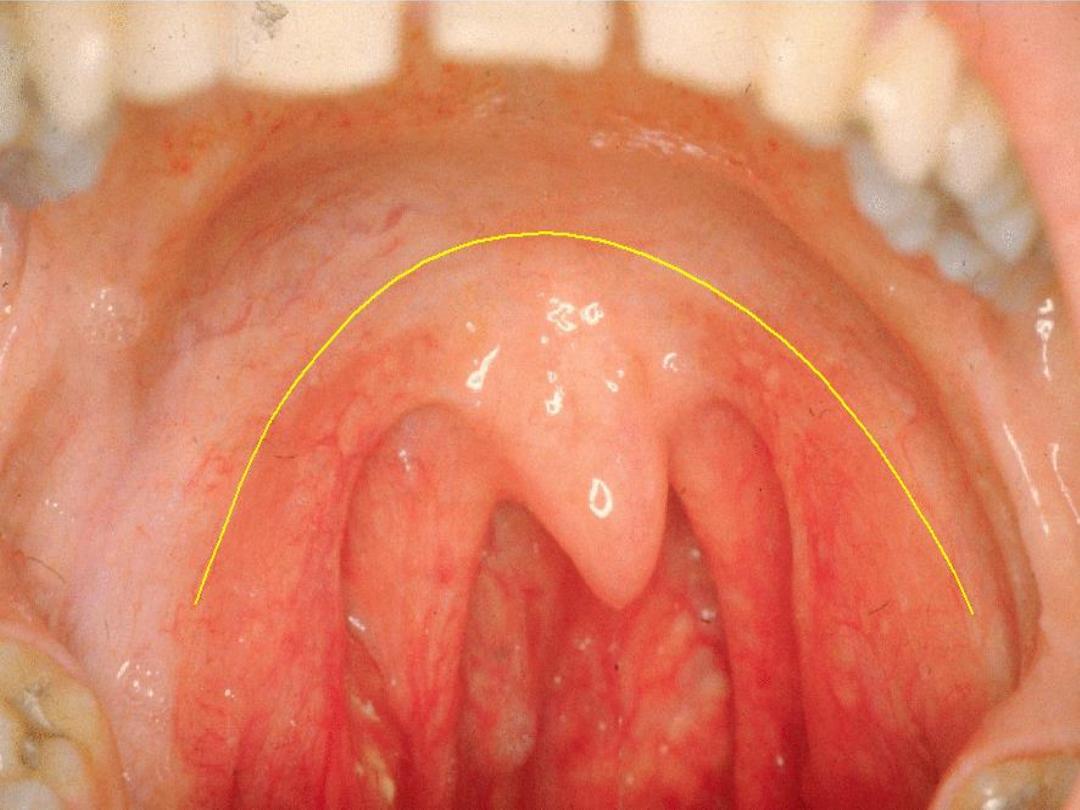

Oropharynx

Extend from the junction of soft and hard palate to the

floor of the valleculae (level of hyoid bone)

Subuints:

1-soft palate 2- base of tongue

3-median and lateral glossogoepglottic folds

4-valleculae 5-posterior pharyngeal wall

Palatine Tonsil

lies in tonsillar fossa between

palatoglossal and palatopharyngel folds and coresponding

muscles, it compose of lymphoid tissue with germinal

center containing 6—20 epithelium-lined crypts. Tonsillar

capsule (thin areolar tissue) separate it from the under

lying superior constrictor

Lingual tonsil

collection of lymphoid

tissue in the base of tongue